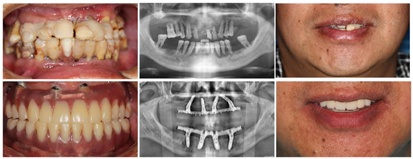

医嘱要求戴牙后1、3、6个月、1年、每半年定期复诊维护,口腔卫生指导,检查修复体、修复配件完整性和稳固性,清洁义齿和基台周围,修理修复体出现的裂纹或折裂部分,检查并局部调整咬合。种植修复后3年X线检查示种植体周围骨结合良好,种植体周围未见明显边缘骨吸收(图16,图17)。

种植修复后义齿使用状况良好,经过治疗周期内多次的健康教育,患者掌握了口腔卫生理念和健康行为,口腔卫生状况改善。植体周健康状况保持良好。通过治疗恢复了相对健康的口腔环境和牙列的完整性,美学效果及咬合功能患者满意(图18)。